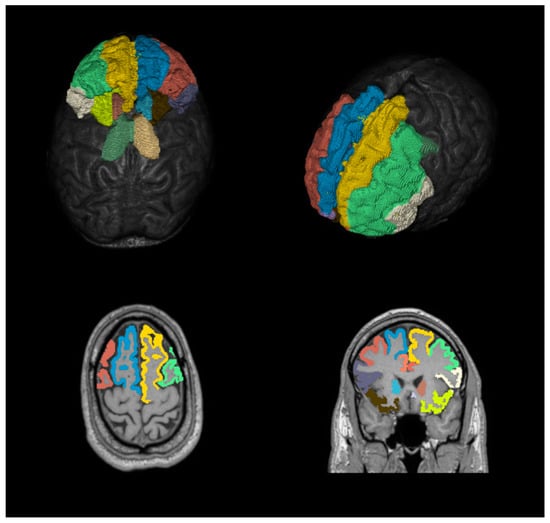

Postprocessing